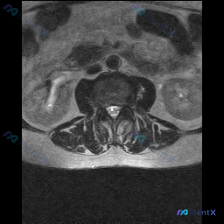

这是一张腰椎MRI T2加权轴位扫描图像,我们逐层拆解结构:

- 椎体与终板:椎体后缘信号正常,低信号符合皮质骨表现,没有明显骨质破坏、水肿,也没有典型Modic终板炎改变

- 椎间盘:髓核信号没有明显减低(没有严重脱水),后缘形态完整,没有明显椎间盘突出征象,硬膜囊前方也没有压迫改变

- 椎管与侧隐窝:中央椎管形态清晰,硬膜囊脑脊液信号饱满,没有狭窄受压,双侧侧隐窝空间正常

- 神经根结构:马尾神经束信号均匀,双侧神经根走行正常,没有受压、推移或包裹

- 韧带与小关节:黄韧带没有增厚,后方小关节间隙清晰,关节面形态正常,没有明显骨赘增生或滑膜囊肿

- 椎旁软组织:双侧竖脊肌体积对称,信号均匀,没有萎缩、脂肪浸润或异常水肿信号